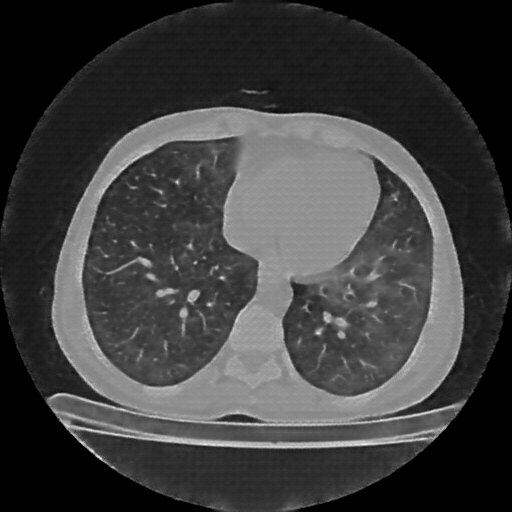

Original VENOUS CT scan

Full window (WL 1023.5, WW 4095 β†’ Low βˆ’1024, High +3071)

Lung window (WL -600, WW 1500 β†’ Low βˆ’1350, High +150)

Mediastinum window (WL 40, WW 400 β†’ Low βˆ’160, High +240)